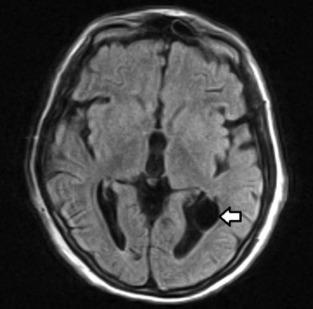

De presentación infrecuente, localizados generalmente en el interior o al lado de los ventrículos laterales.3 Poseen origen neuroectodérmico, formándose por una evaginación del piso del tubo neural.3 En imágenes presentan las características habituales de un quiste simple (►Fig. 10).3

RM de cerebro, corte axial FLAIR; se aprecia en la prolongación occipital del ventrículo lateral izquierdo una imagen de apariencia quística de pared delgada (flecha) compatible con quiste ependimario.